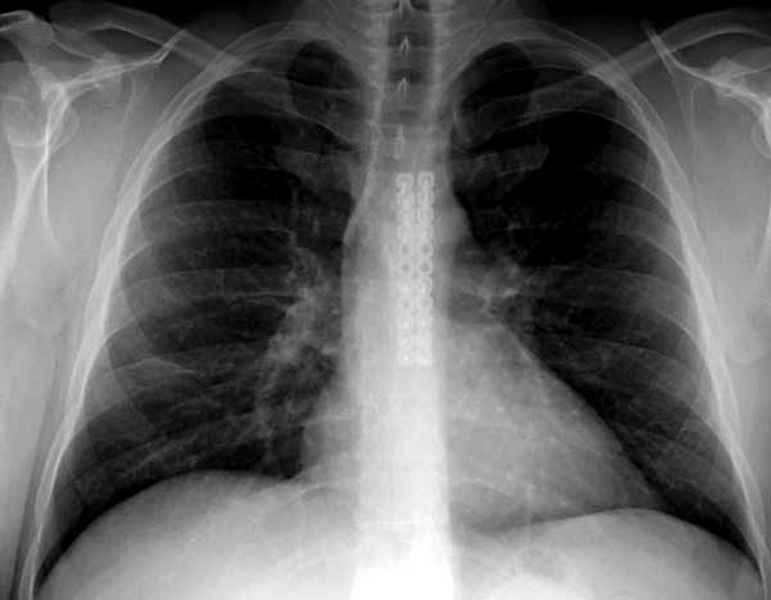

Юра, интересно, насколько такой остеосинтез контролирует степень репозиции, а то у меня имеются снимки девочки 11 лет, направленной ко мне на консультацию из одной из республик бывшего союза.

После торакальной операции, по-видимому, сильно натянули проволоку, и в результате получился захлест отломков в друг друга.

Оперировавший хирург предлагает подождать, а родителей беспокоит проблема прогрессирующей ассиметрии лица, как при кривошее.